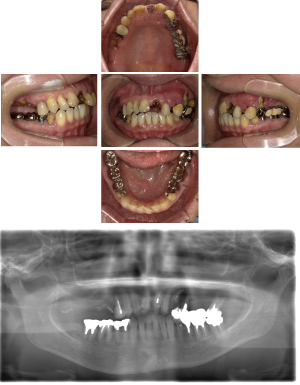

50代 インプラント治療(右上3左上3のみGBR)

| 年代・性別 | 50代・男性 |

| 主訴 | 入れ歯が合わず毎日ヨーグルトしか食べることができないので、しっかり咬めるインプラントにしたい。 |

| 部位 | 右下⑦⑥5④ 上顎③2①①2③ 左下67 |

| 治療期間 | 約9ヶ月 |

| 費用 | ¥4,273,500(税込) |